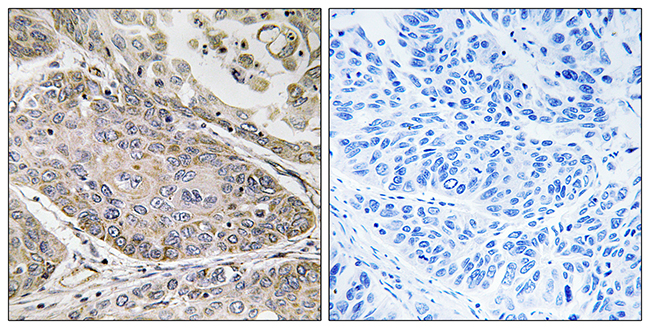

Anti-PLA2G4E AntibodyA99980

ApplicationsELISA, ImmunoHistoChemistry

ReactivityHuman

Anti-PLA2G4D AntibodyA99981

ApplicationsELISA, ImmunoHistoChemistry

ReactivityHuman

Anti-p57KIP2 AntibodyA99982

ApplicationsELISA, ImmunoHistoChemistry

ReactivityHuman